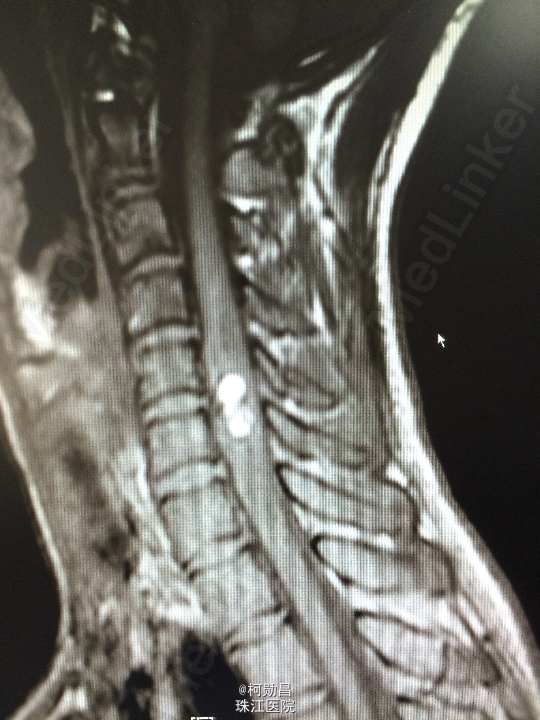

查体:颈椎下端棘突间轻压痛,颈椎活动受限,双臂丛牵拉试验阳性,压头试验阳性。四肢肌力5级,感觉:右侧前臂尺侧小指及无名指痛、触觉稍减退,余肢体及鞍区疼痛觉正常。反射:右侧肱二头肌腱反射亢进,左侧肱二头肌腱反射稍亢进,左侧肱三头肌腱反射活跃,双侧挠骨膜腱反射康静,双侧膝腱反射正常。余反射正常。病理征:右侧Hoffman征弱阳性,左侧Hoffman征正常,余征均正常。 辅助检查:颈4-6椎体水平髓内出血信号,海绵状血管瘤伴出血?

诊断:C5/6脊髓内海绵状血管瘤并出血。 处理:予手术切除治疗